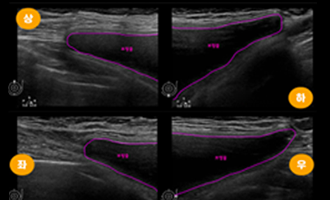

Pre- and Post- Surgery Breast Examination

With breast disease specialists and radiology

experts, we perform precise diagnostics through

mammography, breast ultrasound, and

Mammotome procedures. This one-stop system

ensures thorough evaluation of breast health

and implant condition before and after surgery.

Post-Surgery Implant Assessment

We confirm whether the implants are properly positioned

and monitor for complications such as capsular

contracture, rupture, rippling, or seroma through follow-up

assessments.